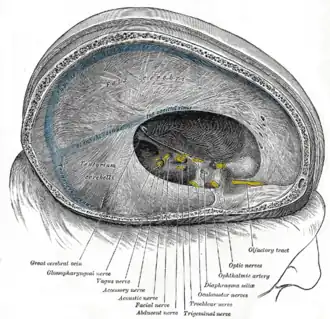

Inferior view of the human brain, with the cranial nerves labeled.

Inferior view of the human brain, with the cranial nerves labeled. -

Dura mater and its processes exposed by removing part of the right half of the skull, and the brain

Dura mater and its processes exposed by removing part of the right half of the skull, and the brain -